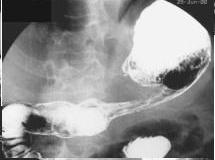

Adenocarcinoma de antre . Image en TOGD

de estomac .Le bord du tumeur est irregulie ,

rigidite et invasive |